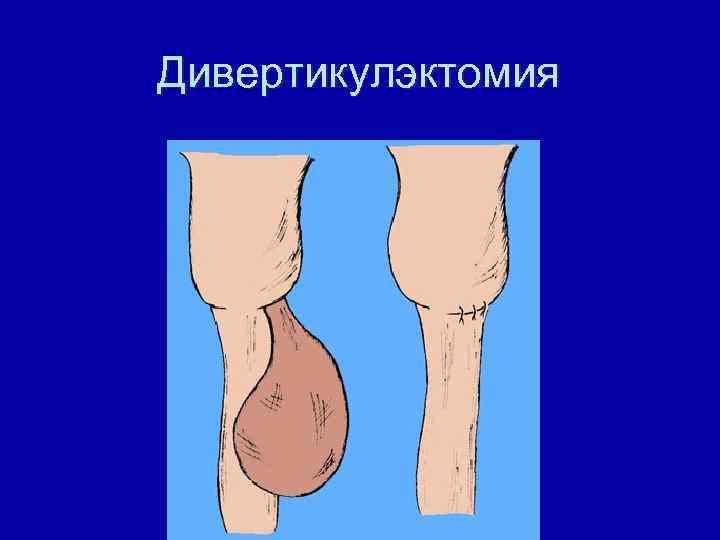

Дивертикулэктомия

Больная П. 49 л. Диагноз: эпифренальный дивертикул.

Больная П. 49 л. 21. 03. 2005 – дивертикулэктомия.